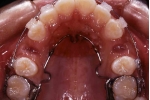

| 治療中

|